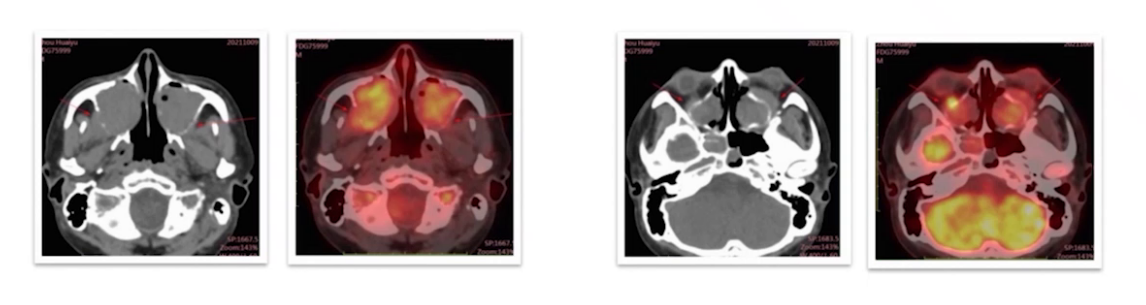

外院PET-CT:1)全组副鼻窦软组织,部分达双侧鼻腔、左侧眼眶球后,SUVmax 19.9;2)右侧下颌骨周围软组织增厚,最大4.4cm×2.4cm,SUVmax 25.6;3)全身多组高代谢淋巴结,SUVmax 12.5,最大 5.3cm×3.6cm;4)胸膜、多发骨代谢增高,均考虑受累。